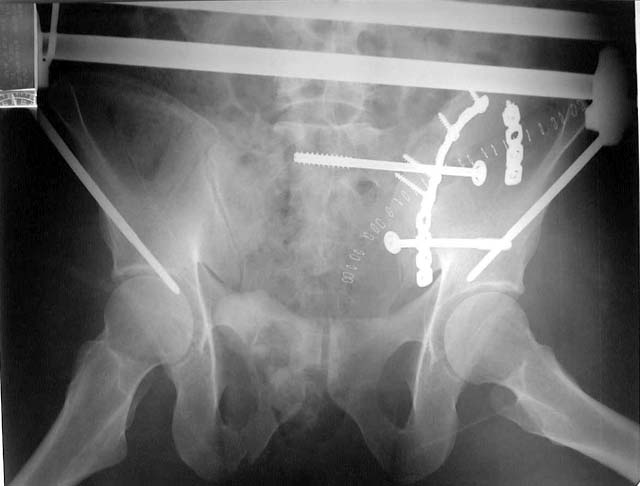

I have attached the pictures of what we did. We got her into the OR the day after injury. We applied manual traction to the thigh and flexed the hip a bit. I pushed the iliac wing medially using a screwdriver placed thru a little stab wound.

Once we had put the wing back together with the front-to-back screw, we pinned the ilium to the sacrum. I was chicken to use S1, due to the dysmorphism, and her S2 body was a big, easy shot.

The ramus fractures still had a little motion with stress, so we fixed them, too. Then we ORIF'd her supracondylar femur fx. It was a shattered mess.

She's doing okay so far. Her knee is going to be her biggest problem, I think.

Postop AP

Postop Inlet

Postop Outlet